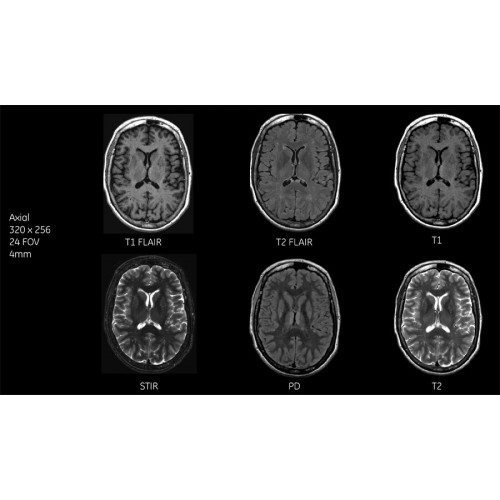

Система SIGNA Pioneer воплощает поразительные достижения в области визуализации. Передовая технология Total Digital Imaging (TDI) позволяет добиться большей четкости изображений и на четверть повысить соотношение сигнал/шум.

Благодаря революционному программному пакету Silent Suite уровень шума снижается до 77 дБ, что всего на 3 дБ выше уровня окружающей среды. Программный пакет Silent Suite теперь включает полный пакет приложений для исследования ЦНС (T1, T2 FLAIR, DWI10, МРА). Кроме того, мы расширили возможности визуализации Silent за пределы ЦНС для исследований скелетно-мышечной системы и позвоночника. Silent Suite – платформа, содержащая в себе все импульсные последовательности для бесшумного сканирования.